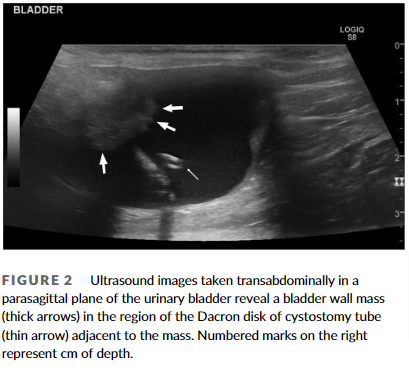

사진처럼 방광내측으로 암지 자라서 증식한 양상이다.

이 증례가 임상가에게 주는 가장 큰 교훈은 장기적인 방광루 튜브와 같은 요로 삽입 장치가 고양이에서 만성적인 염증을 유발하여 요로상피암(UC)과 같은 악성 종양의 발생 위험을 높일 수 있다는 점입니다. 이는 사람에서 장기적인 요도 카테터 사용이 방광암과 관련이 있는 것과 유사한 패턴을 보입니다. 따라서, 장기적인 요로 삽입 장치 사용 시 지속적인 모니터링과 정기적인 검사를 통해 초기 단계에서 종양 발생을 확인하고 조기에 개입하는 것이 중요하다는 점을 시사합니다. 특히, 만성적인 무균성 방광염과 같은 염증 증상이 지속될 경우, 종양 발생 가능성을 염두에 두고 보다 적극적인 진단과 관리가 필요합니다.